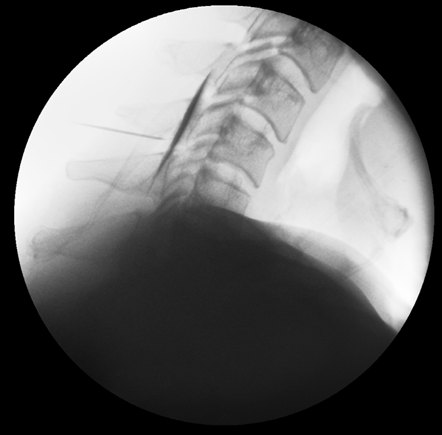

그림6.png

<앞선 환자분의 치료 영상인데요. 이렇게 C-arm을 보면서 진행하기 때문에 영상까지 남을 수 있게 된답니다. ^^>